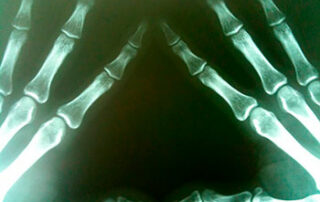

- Mão ou Quirodáctilos;

- Mãos e Punhos para Idade Óssea;